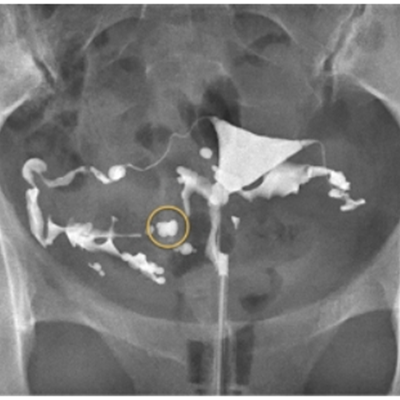

子宮卵管造影(hysterosalpingography:HSG)は、造影剤を子宮腔内に注入し、子宮内腔、卵管の陰影から子宮腔の状態、卵管の疎通性および骨盤腔内の癒着を判定する検査です。

不妊患者におけるX線像

不妊患者852例中75例(8.8%)に脈管内侵入がみられましたが、臨床症状を呈したものはなく、アレルギー反応も認められませんでした。